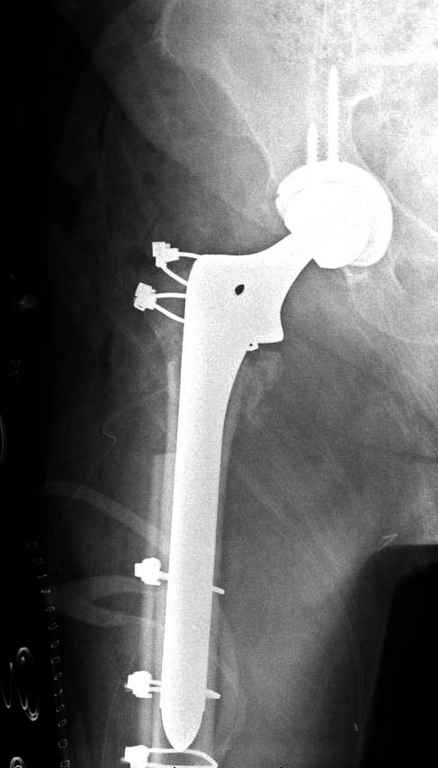

В данном случае в головке бедра и в вертлужной впадине огромный дефект, навряд ли удалением импланта или заменой на другой можно сохранить сустав.

Вашему вниманию представляется похожий случай, пациентке 70, осложнился в течение одного месяца после операции. Ревизия с заменой сустава, кабельная фиксация на трохантер. При установке в дистальном диафизе обнаружен тонкий кортикальный слой и сделана профилактика от возможного перелома аллографтом.